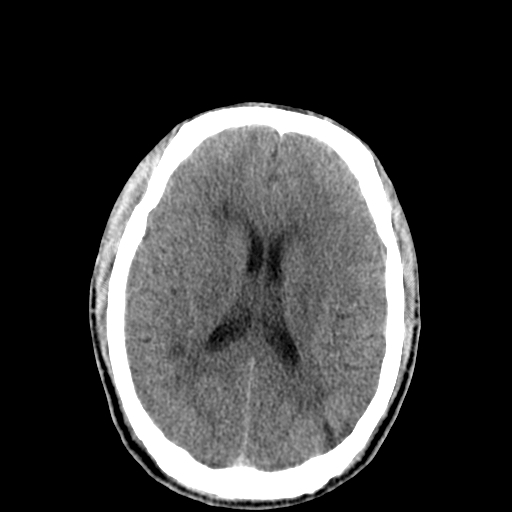

以下是引用李衡钧在2008-9-18 17:37:00的发言:[br]脑质内见两个低密度灶,其内见点状高密度。[br]考虑脑囊虫。建议增强或进一步检查确诊。

以下是引用chmh在2008-9-18 18:45:00的发言:[br]考虑脑囊虫病可能性大,建议行ct增强检查及血清和脑脊液囊虫补体结合试验.